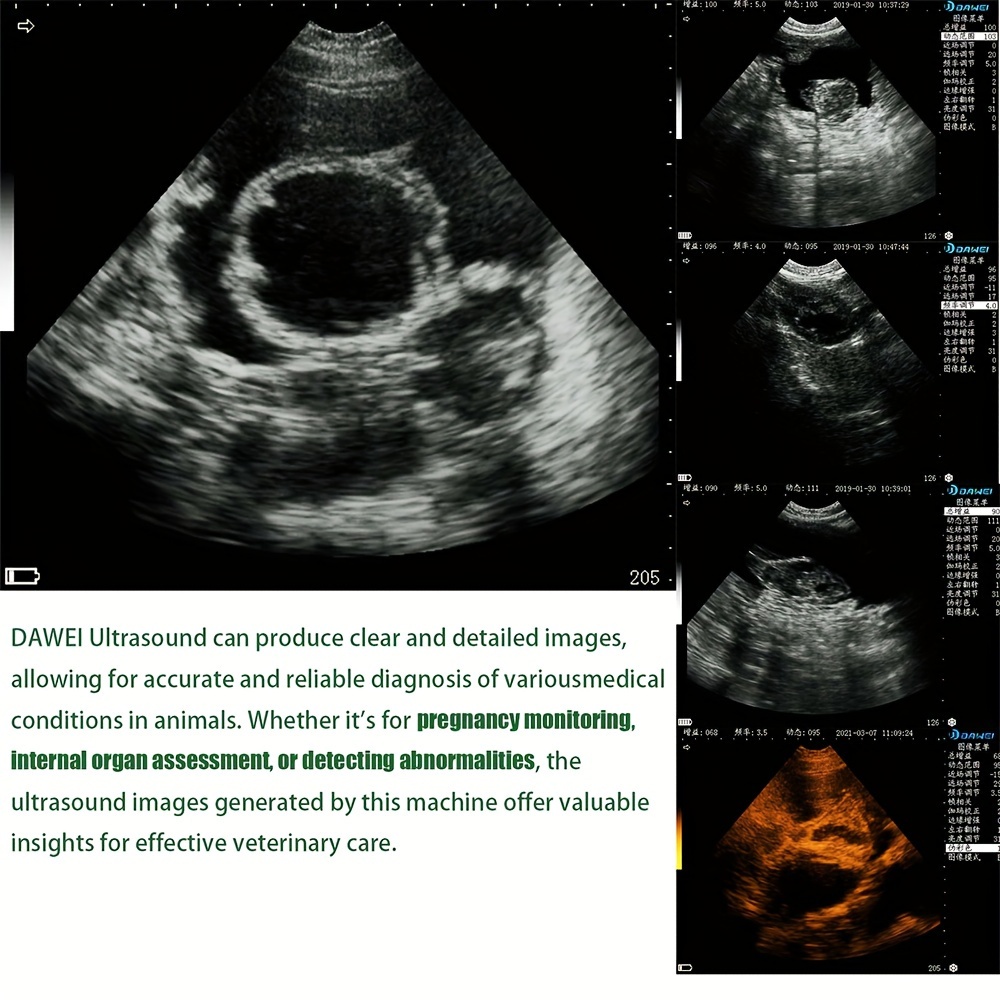

3.5MHz Probe: Ideal For Ultrasound Imaging And Pregnancy Testing Of Medium-sized Animals Such As Pigs, Sheep, Dogs, Etc

DAWEI-S0 Is A Portable Veterinary Ultrasound (B-ultrasound) Diagnostic Instrument. Its Superior Product Performance And Ergonomic Handheld Design Bring More Convenience To Users During Testing.